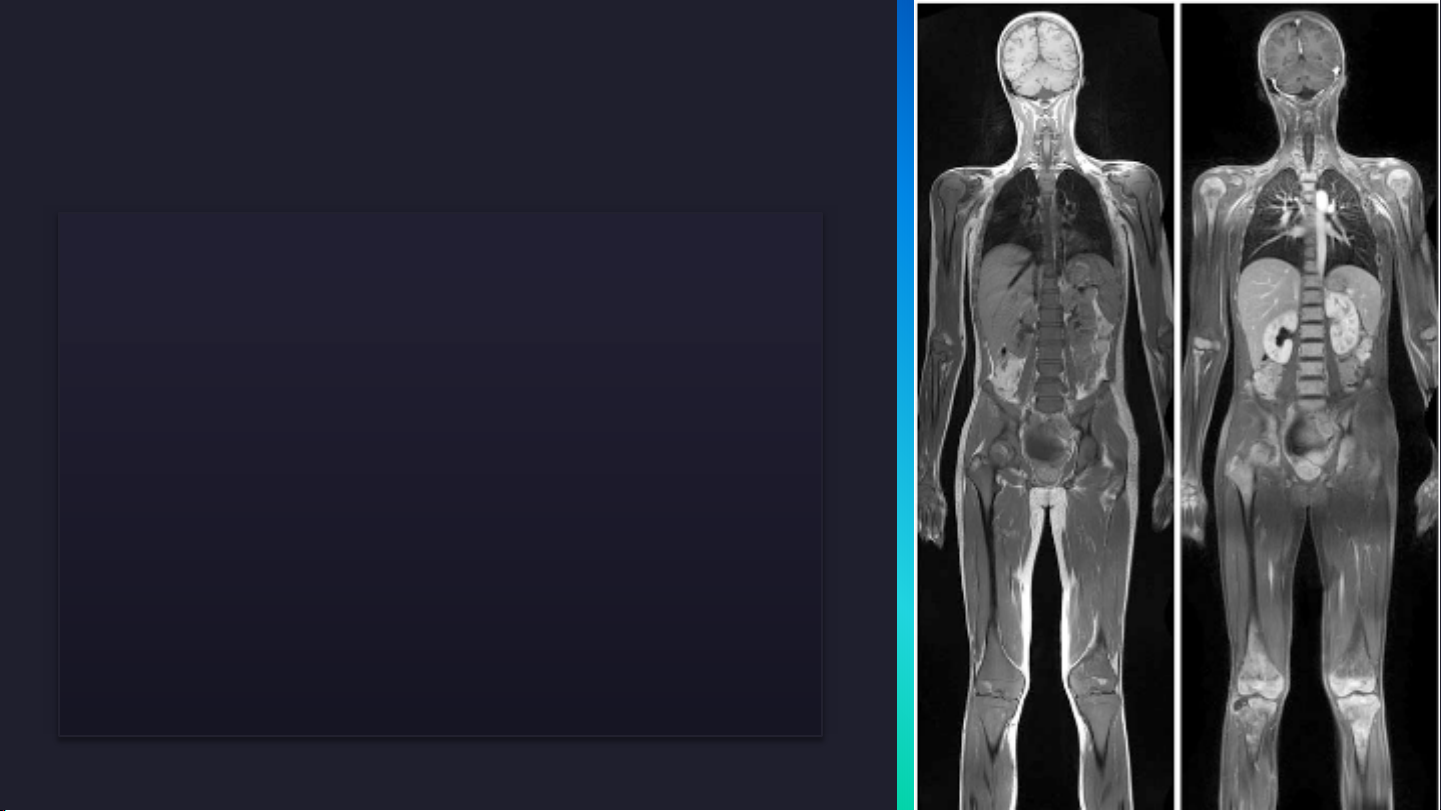

MRCP với TE=678ms trên máy

MRI SIEMENS Avanto 1.5T [1]

Hình ảnh MRCP với TE=650ms trên máy

MRI Hitachi ECHELON 1.5T